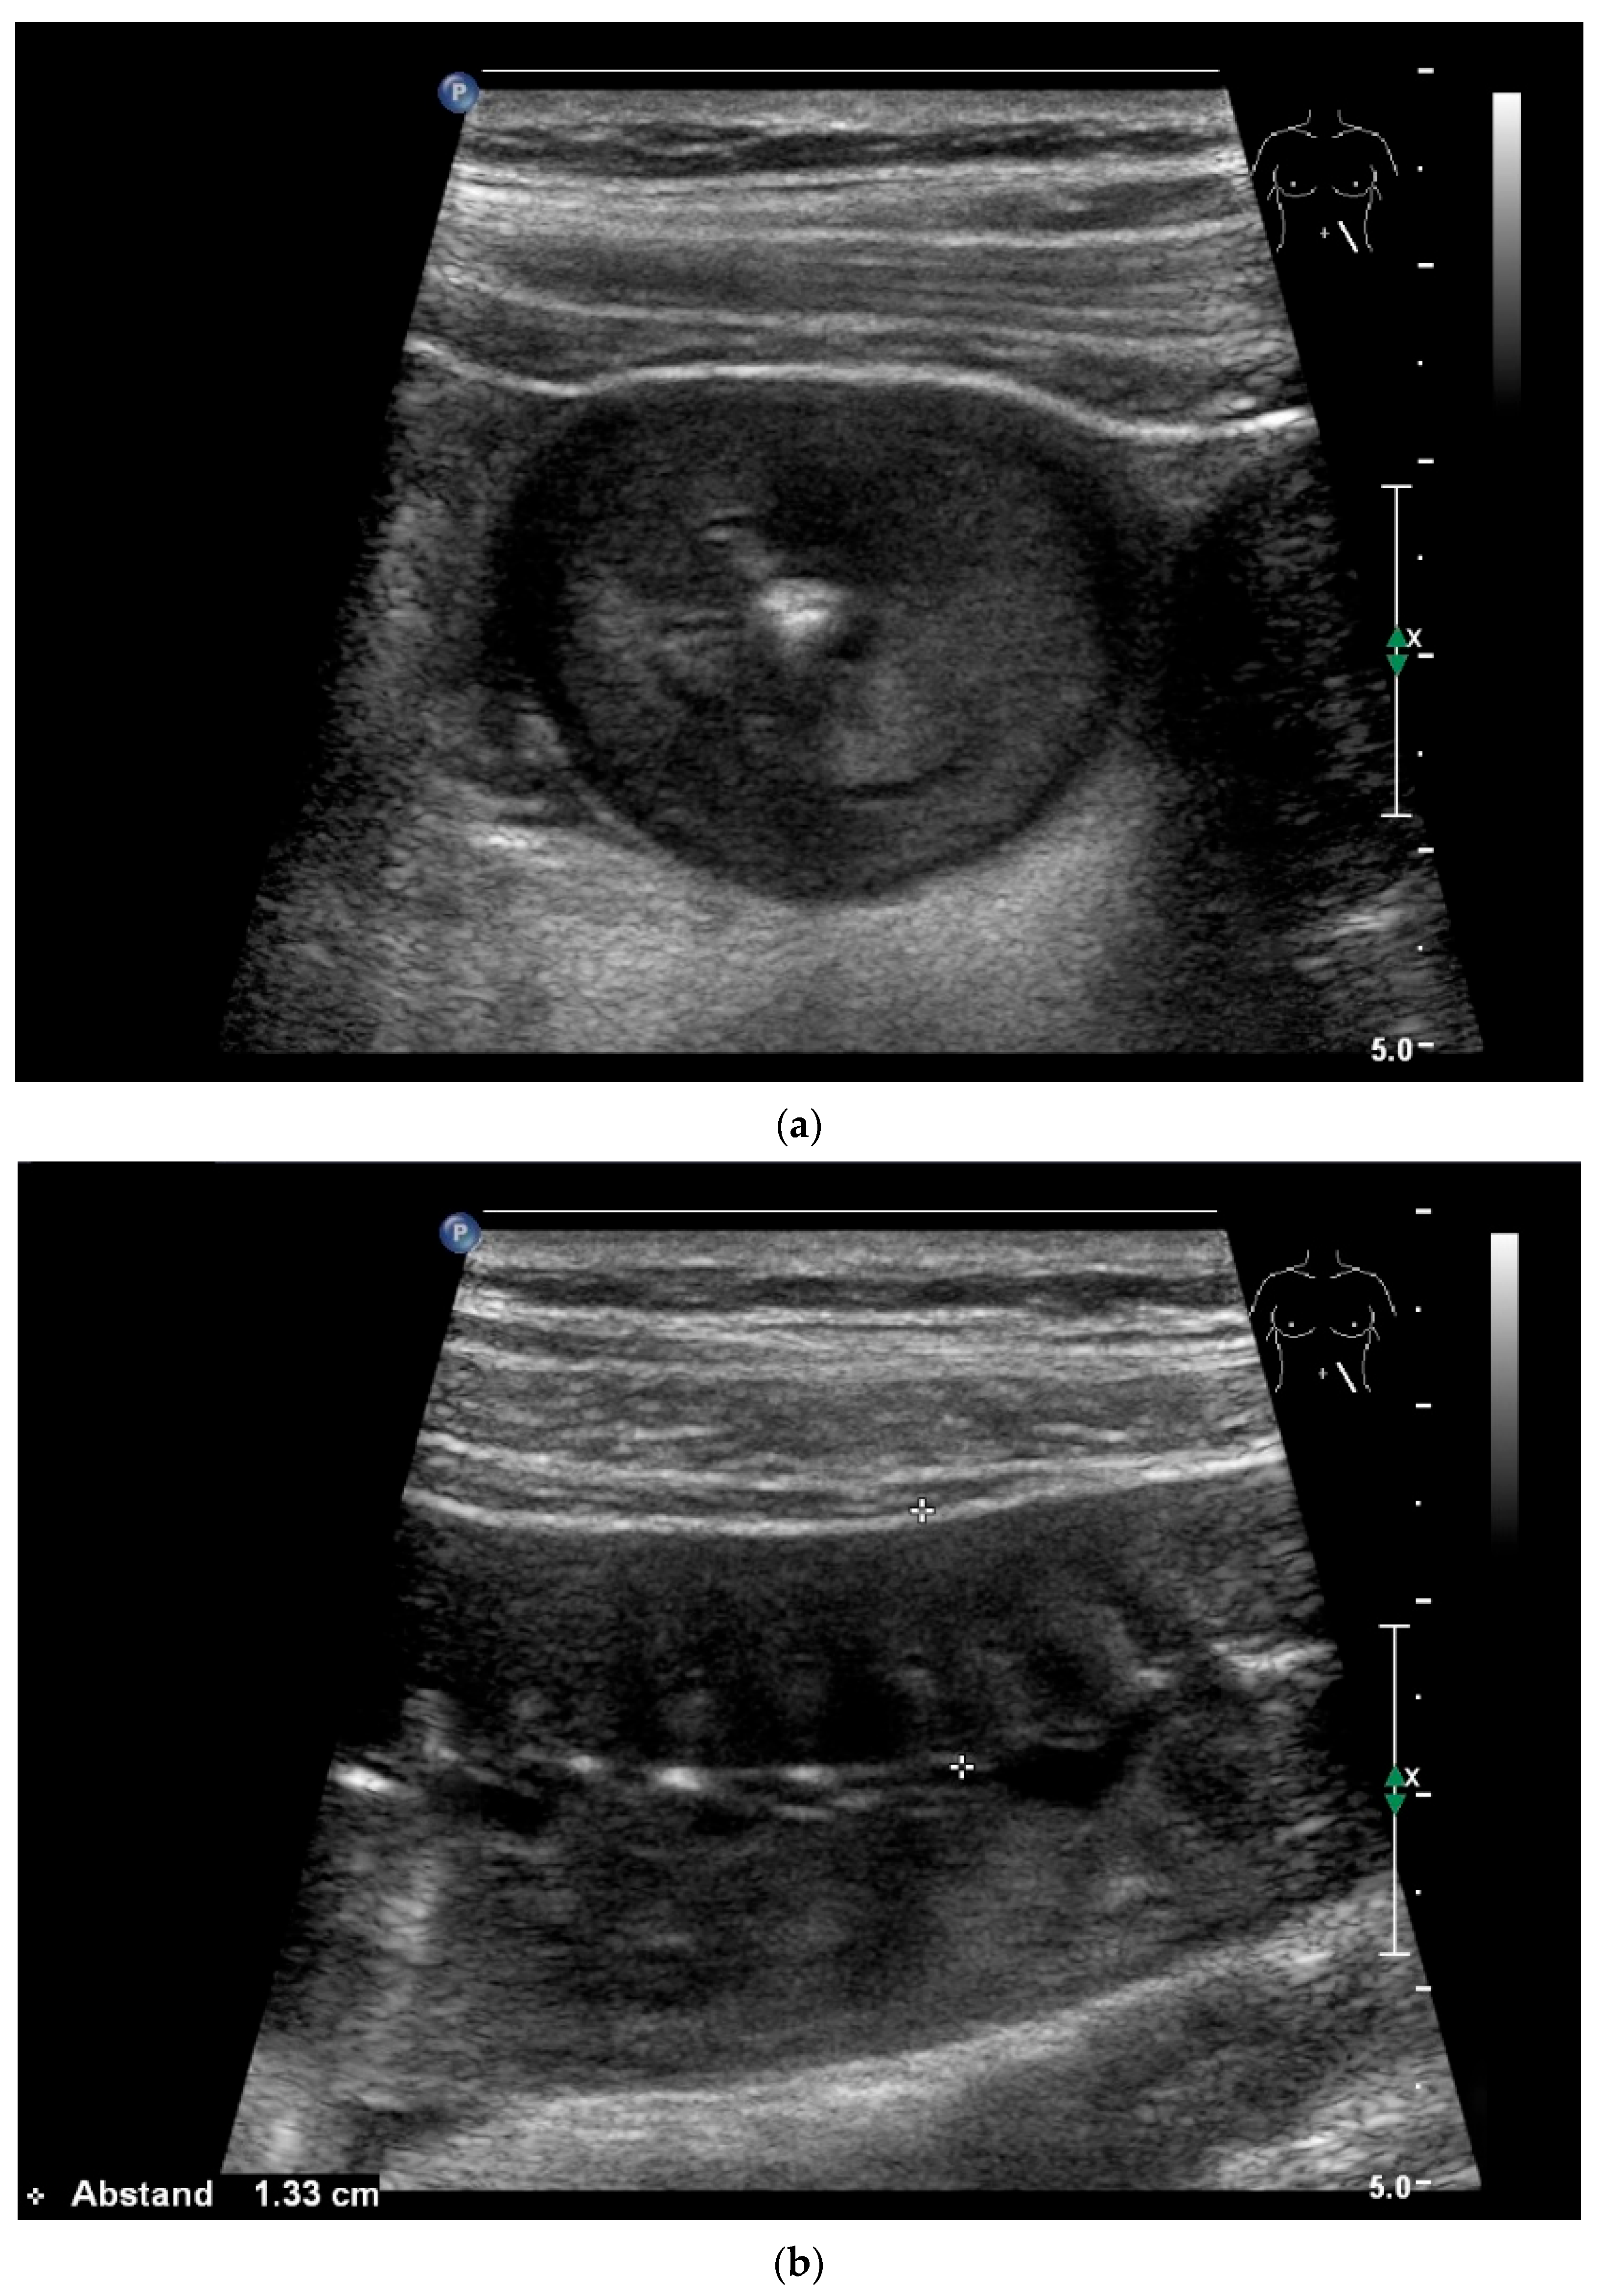

Figure 3.

Intussusception. In the ileum, the intestine is inverted. Instead of the usual five layers, there are many onion-skin-like layers (a). The intestine is folded in on itself several times. The wall is marked with arrows (b).

Figure 4.

NEN in the ileum: an approximately 14 mm hypoechoic nodular tumor is visible (a). Subsequently, peristalsis reveals a hypoechoic wall thickening (W) and hyperechoic luminal reflex (L) (b) and, finally, causes the tumor to be obscured by the luminal contents and dorsal artifacts (c). The region of the tumor is marked with a yellow arrow in all three images.